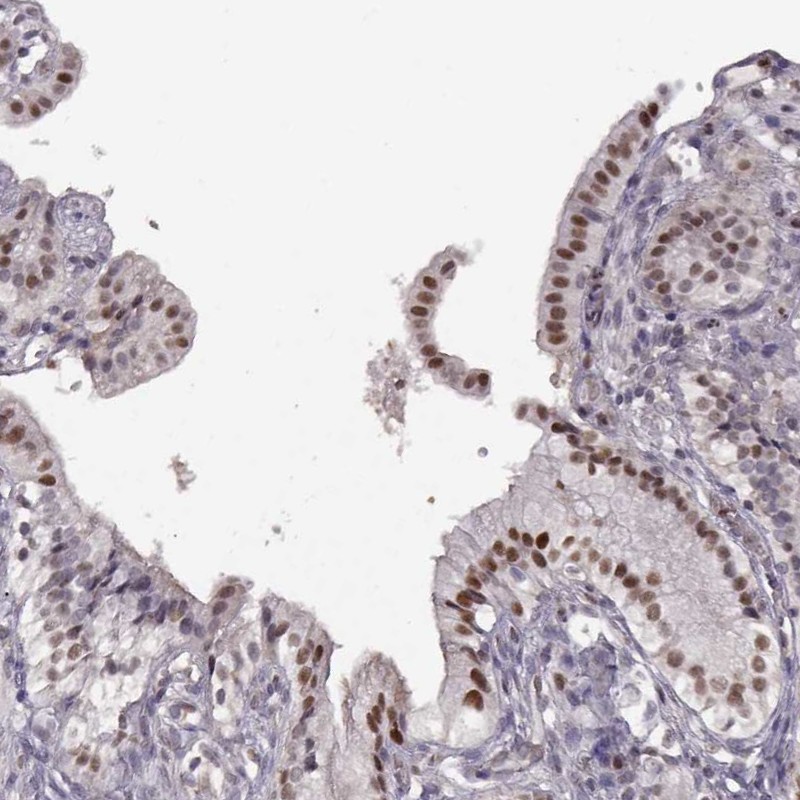

Immunohistochemical staining of human gallbladder shows strong nuclear positivity in glandular cells.